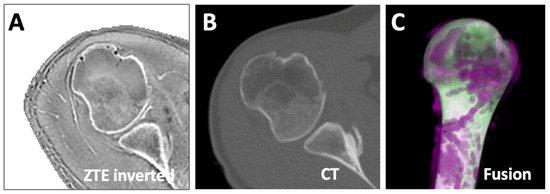

Figure 2.

Inverted axial ZTE shoulder images used in this study were acquired with moderately varying scan parameters. (A) was acquired with TR = 88 ms, TE = 0.016 ms, FOV = 180 mm, matrix = 256 × 256, and 1 mm slice thickness. (B) was acquired with TR = 458 ms, TE = 0.016 ms, FOV = 160 mm, matrix = 256 × 256, and 1 mm slice thickness. (C) was similar to (B) but acquired with FOV = 180 mm, matrix = 512 × 512, and 1.2 mm slice thickness. While varying in image contrast, all images shared a similar feature of depicting the bones of the shoulder with high signal intensity.